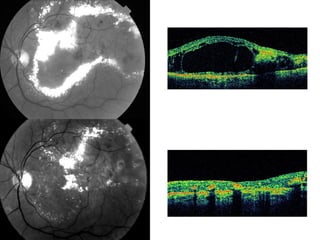

Les occlusions veineuses rétiniennes (OVR) touchent entre 6.000 et 60.000 nouveaux patients par an, avec un âge moyen de diagnostic de 57 ans pour les OVR et 65 ans pour les autres formes. Les causes et l'évolution de la maladie sont souvent imprévisibles, avec des traitements divers allant des médicaments à la chirurgie, mais les complications comme l'œdème maculaire demeurent fréquentes. Les traitements potentiels comme les injections intra-vitréennes peuvent entraîner des effets indésirables, dont un risque accru de cataracte.